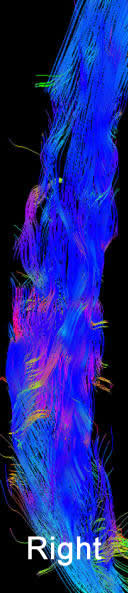

MRI of the dorsal spine with contrast and myelography and fibertraking and spectroscopy showing the recent lesions as seen in the below pictures with abscess formation.

MRI showing the new flare with abscess malformation and the old one

Fibertraking of the spinal cord at the lesion showing some scanty fibers ready for attack from behind (The middle picture)